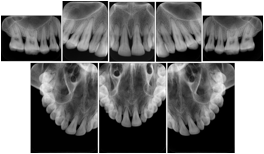

- OO-1. Intra-oral Full Mouth Series Structured Display